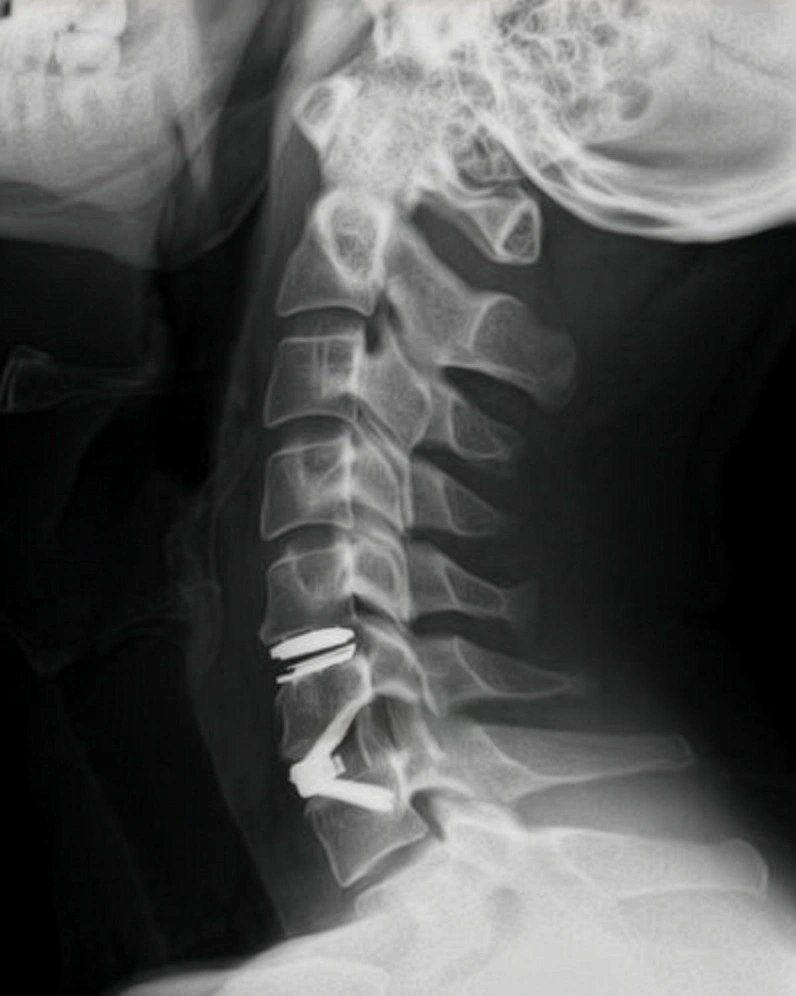

Per l’ernia del disco e la discopatia cervicale, responsabili di cervicalgia, cervicobrachialgia e, nei casi più avanzati, di mielopatia cervicale, Villa dei Fiori propone interventi mirati a decomprimere le radici nervose e il midollo spinale, preservando per quanto possibile la biomeccanica del rachide.

A seconda del tipo di lesione, del numero di livelli interessati e dell’assetto della colonna, si possono utilizzare approcci anteriori o posteriori. Le tecniche più frequentemente impiegate prevedono la rimozione microchirurgica del disco erniato attraverso un accesso anteriore al collo. Una volta liberate le strutture nervose, lo spazio discale viene sostituito:

• con una protesi discale cervicale, quando si vuole mantenere la mobilità del segmento;

• con una cage (gabbietta) in materiale sintetico, spesso associata a placca anteriore, quando è indicata una fusione stabile tra le vertebre.

L’uso di cage moderne, spesso riempite con materiale osteoinducente o con piccoli frammenti ossei del paziente, ha reso queste procedure più rapide e meno invasive rispetto al passato. Il decorso è generalmente confortevole: il paziente viene mobilizzato precocemente e, nella maggior parte dei casi, può tornare in breve tempo alle normali attività, con un progressivo recupero della funzionalità e una netta riduzione del dolore.